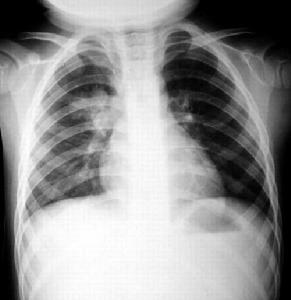

普通透視檢查X線表現為多葉瀰漫性斑片狀浸潤陰影,以兩下肺為主偶有實變徵象常可發現中等大小的膿腔形成和胸腔積液,膿胸也多見。